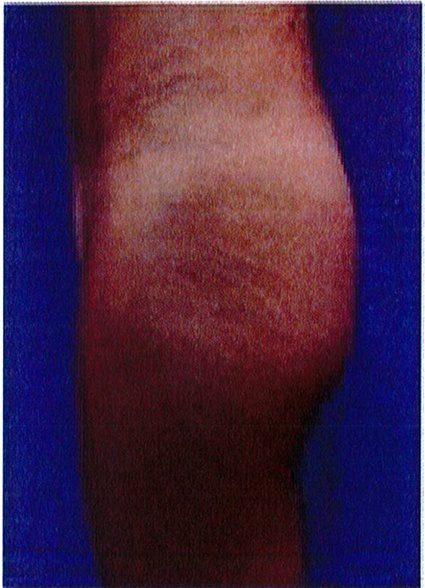

Bệnh nhân 52 tuổi xuất hiện chùng da vùng mông (mức độ nặng), mong muốn giải quyết vấn đề này đồng thời tăng kích thước vòng ba. Hai khối anatomic implant

Hình. 19. . (A) Hình anh trước và (B) và sau phẫu thuật làm đầy mông của bệnh nhân chùng da vùng mông tương đối nhiều. Bệnh nhân được đặt khối implant dưới cân thể tích 330 mL ở hai bên.